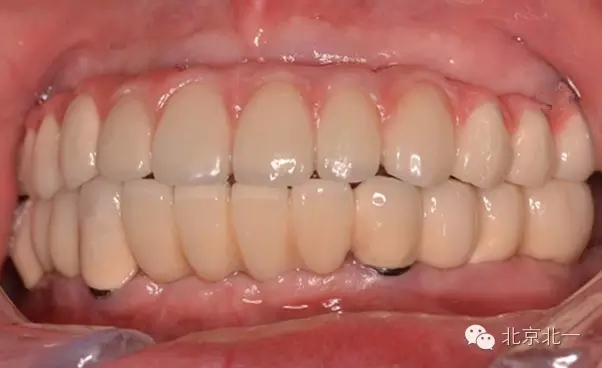

圖六:永久修復(fù)戴牙后照片

圖七:永久戴牙后照片